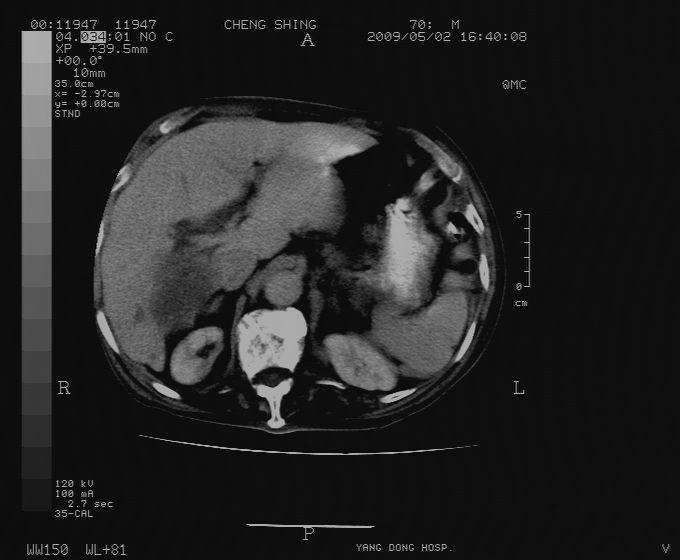

标题: CT19743:男70岁,肺部疾病入院,B超发现肝右叶占位,CT [打印本页]

标题: CT19743:男70岁,肺部疾病入院,B超发现肝右叶占位,CT

肝表面塌陷,病灶周围有子灶,前面较大子灶强化符合肝癌表现,考虑肝癌肝转移可能性大.

1)考虑肝癌并肝内转移。2)少量腹水。3)双侧胸腔积液。

1)考虑肝癌并肝内转移。2)少量腹水及双侧胸腔积液。3)椎体退变。